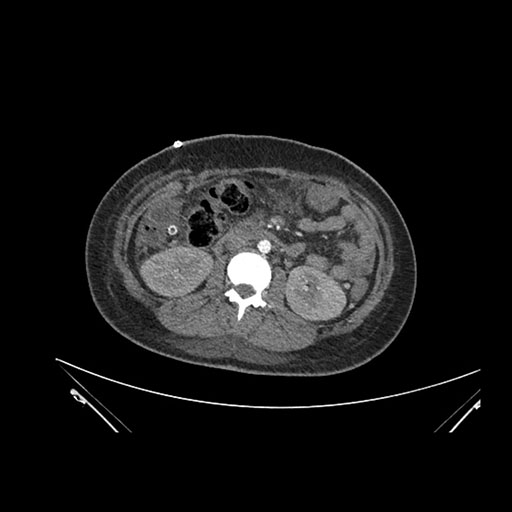

Axial Arterial

Axial Venous

Imaging analysis

Based on initial findings, which issue(s) would you be most concerned about?